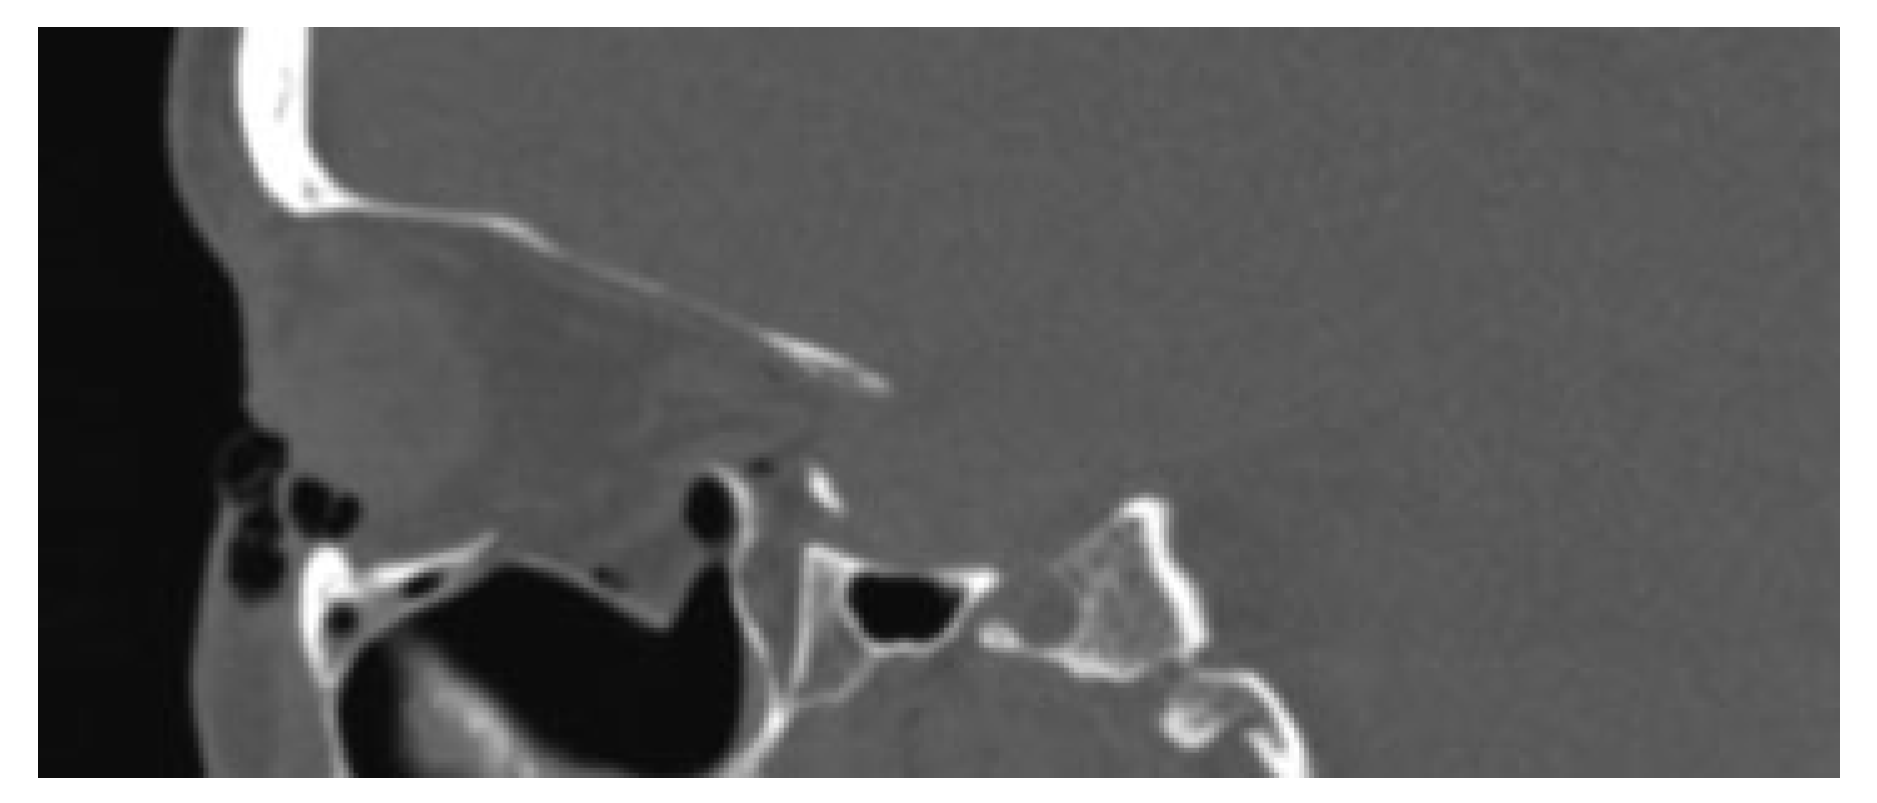

A 59-year-old female presented to the maxillofacial outpatient department following a mechanical fall resulting in a left orbital floor fracture. Enophthalmos of 2 mm was present and a CT scan revealed a large floor defect (Figure 2 and Figure 3). Diplopia was present on upward gaze. A rapid prototyping model was fabricated and a Synthes titanium orbital plate was further adapted preoperatively. The orbital floor was accessed via a mid-lid approach and the modified titanium orbital plate was inserted. No further adaptation of the plate was required and the time taken from insertion of the plate to final fixation was less than 1 minute, as no further adaptation was necessary. Position was confirmed with an intraoperative CT scan (O-arm, Medtronic [Medtronic, Minneapolis, MN]) (Figure 4, Figure 5 and Figure 6). The patient’s diplopia and enophthalmos had resolved 2 weeks postoperatively and no complications were noted at the 6th week follow-up.

Figure 3.

Sagittal section of posterior orbital floor defect in case 1.